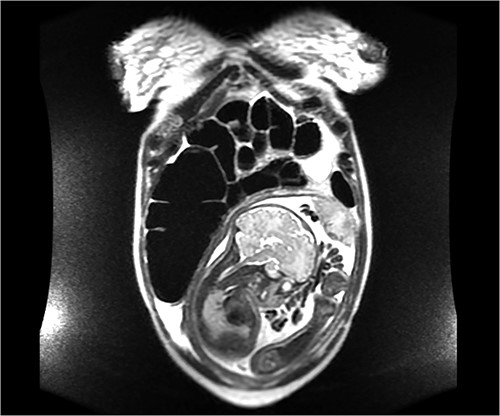

On hospital day 2, the patient became obstipated, and her abdominal exam had notable distension with persistent right upper quadrant tenderness. An abdominal magnetic resonance imaging (MRI) was performed revealing dilated small intestine with air-fluid levels and an inverted-appearing, prominent cecum (Figs. 1 and 2). The patient was diagnosed with an acute abdomen from probable cecal volvulus versus appendicitis and was urgently taken to the operating room for cesarean section (c-section) to facilitate abdominal exploration. After delivery of the child, a cecal bascule was found, with a severely distended cecum (Fig. 3). Because the cecum and ascending colon were deserosalized, a right hemicolectomy with primary ileocolic anastomosis was performed. The patient had return of bowel function on post operative day 5 and was discharged home on day 7.

Axial image of an abdominal MRI on a 36-week pregnant patient with a dilated cecum anteriorly displaced to the ascending colon. Arrows mark the point of inflection.

Coronal image of the same MRI showing a dilated cecum displaced superiorly, consistent with a cecal bascule.

Another cause for the delay in diagnosis is the clinician’s hesitancy to order diagnostic radiologic imaging in pregnant patients due to the fear of harm to the fetus [22, 23]. The opinion of the American College of Obstetricians and Gynecologists is that the radiation exposure of plain X-ray, CT or nuclear medicine technology is at a dose much lower than the exposure associated with fetal harm and that the maternal benefit from early and accurate diagnosis of acute processes such as appendicitis or bowel obstruction outweighs the theoretical fetal risks [24]. Yet, US and MRI are not associated with fetal risk and should therefore be considered first when available. The utility of US for diagnosing a cecal bascule or other bowel obstruction is poor as evidenced by the normal US in the case reports by Lazarus and ours [9]. However, US is still recommended in the pregnant patient with abdominal pain because of its safety and ability to diagnose obstetric or gynecologic etiologies for pain [9]. A cecal bascule on plain abdominal X-ray is characterized by distension of the cecum, paucity of gas in the distal colon, dilated small bowel and gas shadow within the pelvis [3]. CT scan shows displacement of the cecum to the upper or central abdomen, the ileocecal valve to the right upper quadrant and a transition zone between cecum and ascending colon [3]. The sensitivity of diagnosing a cecal bascule in a nonpregnant patient by CT scan is 61% [3]. Diagnosis of cecal bascule by MRI was not found in literature. The MRI for our patient showed an anterior and superior inversion of the cecum.